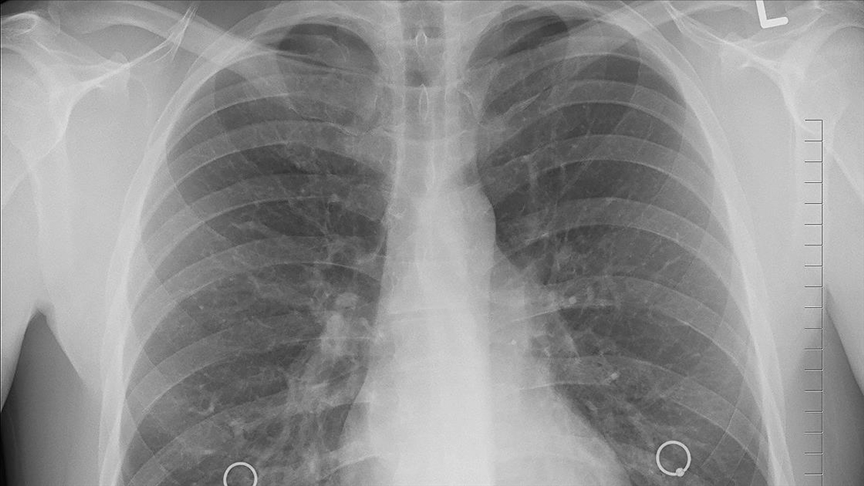

Akciğer kanseri tespiti için geliştirilen yeni kan testi, FT-IR mikrospektroskopisi adı verilen ileri bir teknolojiyi kullanıyor. Bu teknik, kandaki tek bir akciğer kanseri hücresini bile tespit edebilecek hassasiyete sahip. Akciğer kanseri hücreleri, sağlıklı hücrelere kıyasla kızılötesi ışığı farklı şekilde emiyor. Bu farklılık, akciğer kanseri hücrelerinin kimyasal parmak izi olarak tanımlanmasını sağlıyor.

Araştırmacılar, akciğer kanseri hücrelerinin tümör oluşmadan önce bile kan dolaşımına karışabildiğini belirtiyor. Akciğer kanseri bu aşamada klasik görüntüleme yöntemleriyle fark edilemiyor. Yeni geliştirilen test sayesinde, akciğer kanseri hücreleri kan örneği üzerinden tespit edilebiliyor. Böylece akciğer kanseri çok erken bir evrede yakalanabiliyor.